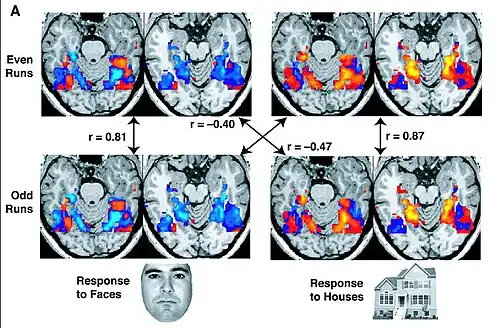

Cognitive and affective "paths": brain imaging data

Research using functional magnetic resonance imaging of the brain suggests that cognitive and affective-expressive forms of communication and self-reflection have distinct neural bases.[50] Clinical findings have long suggested that verbalizations are often very incoherent when the individual is trying to put into words something deeply emotional.[51] Identification of words naming emotions (happy, neutral, sad) was found to be faster than identification of corresponding facial expressions. Recognition of face expressions was more difficult to suppress in favor of the recognition of words than vice versa, the two conditions presenting different patterns of brain activation. These experimental results suggest that reading and recognition of face expressions are stimulus-dependent and perhaps hierarchical behaviors, hence recruiting distinct regions of the medial prefrontal cortex.[48]

Research indicates that the representations of faces and objects in ventral temporal cortex are widely distributed and overlapping, face stimuli eliciting response patterns distinct from those elicited by object stimuli.[49]